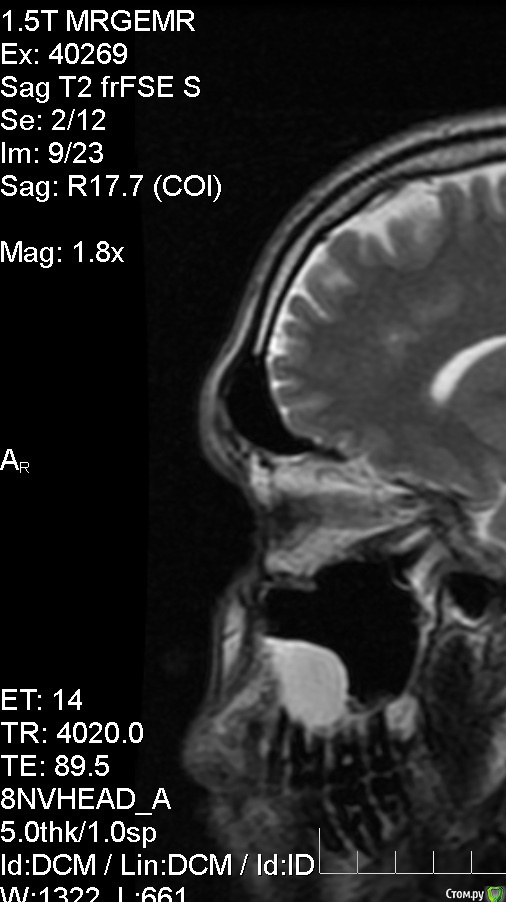

Сделал МРТ головного мозга с контрастом и без, в мозге патологий не выявлено, по заключению киста верхечюлестной правой пазухи. МРТ делал по причине непонятного тянущего ощущения в правой половине головы, не боль, просто стал себя чувствовать не как обычно. Ходил к лору, еле убедил вставить диск и посмотреть снимки, на, что получил ответ, что это от зубов и дорога моя к стоматологу. Высказала мнение, что достаточно вылечить зубы и корни, а кисту можно не трогать. Хочу получить мнение со стороны, и примерную тактику лечения в таких случаях.

Анамнез: уже 1.5 года немного воспалены/набухшие (гингивит?) края десны на верхней челюсти у 8,7,6,5 зуба, больше у 7 и 6. (Небольшая кровоточивость при чистки) На ощупь десны не болят, и зубы тоже. В них нет пломб. После заключения стал ощущать еле заметную тяжесть над перечисленными зубами.

Прилагаю фото снимков.